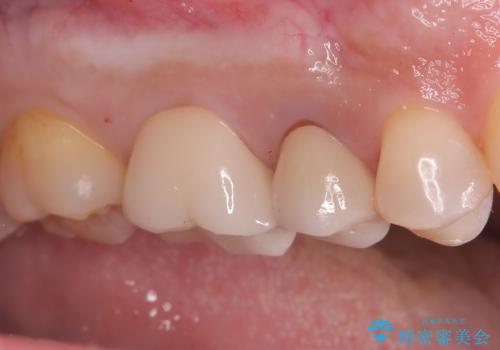

奥歯の銀歯を美しく一新!歯の破折を防ぐセラミッククラウン

- 長年使用してきた奥歯の古い銀歯のやりかえを主訴にご来院されました。診査の結果、銀歯の下の歯質が薄くなっている部分があり、今後強い力が加わると歯が割れてしまう(破折)リスクが高いと判明しました。このリスクを回避し、歯を長期的に守るため、歯全体をしっかり覆う**セラミッククラウン(被せ物)**による修復を提案。機能的な強度と自然な見た目の両立を目指しました。

治療では、まず古い銀歯を慎重に取り外し、内部の虫歯の有無を確認しました。その後、残っている歯質を保護し、強度を高めるために、適合性に優れたオールセラミッククラウンを作製・装着しました。

審美性: 天然歯に近い透明感と色調を持つため、銀歯の時と比べて格段に自然で美しい見た目になります。